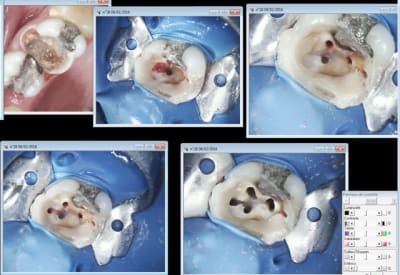

Miracle la 26 était vivante. -))))

Pas facile de trouver les 4 canaux c'est le Mv1 qui a été le plus dur une fois n'est pas coutume ! -)))

Le reste va dégager chez le stomato. J'ai viré la 24 en en chiant assez comme ca après l'endo de 26. Chacun doit faire sa B.A. -)))

J'ai juste la place de faire une ceram sur 26 une fois que 36 sera enlevée. -))))

Tu travailles sous microscope électronique?

ca coute combien (à financer et à honorer par le patient)?

Ah ouai j'avais pas bien regardé les photos. Comment as-tu trouvé MV1, parce que sur la photo en haut à droite on ne le voit pas du tout.

Bien! y touche sa bille chicot29, belle ouvrage

Le feeling et un bon sx protaper. -)))

Et pour les photos c'est un microscope ou c'est une caméra endobuccale?

C'est vrai ma reconstitution préendo était bien collée à l'entrée du MV1 dommage que le patient consultait à cause de douleurs. Il serait venu 15 jours avant ca aurait pu le faire. -)

En même temps, dans ton cas, un onlay est une reconstitution pré-endo de luxe :)

On est quand même d accord que toute considération financière mise à part, on est en plein dans l indication d'un onlay là?

Ha non à ce degré de saleté et de négligence on est hors indication d'un onlay pour moi.

On est pile-poil dans l'indication d'une CCM avec un sertissage périphérique légèrement sous-gingival.